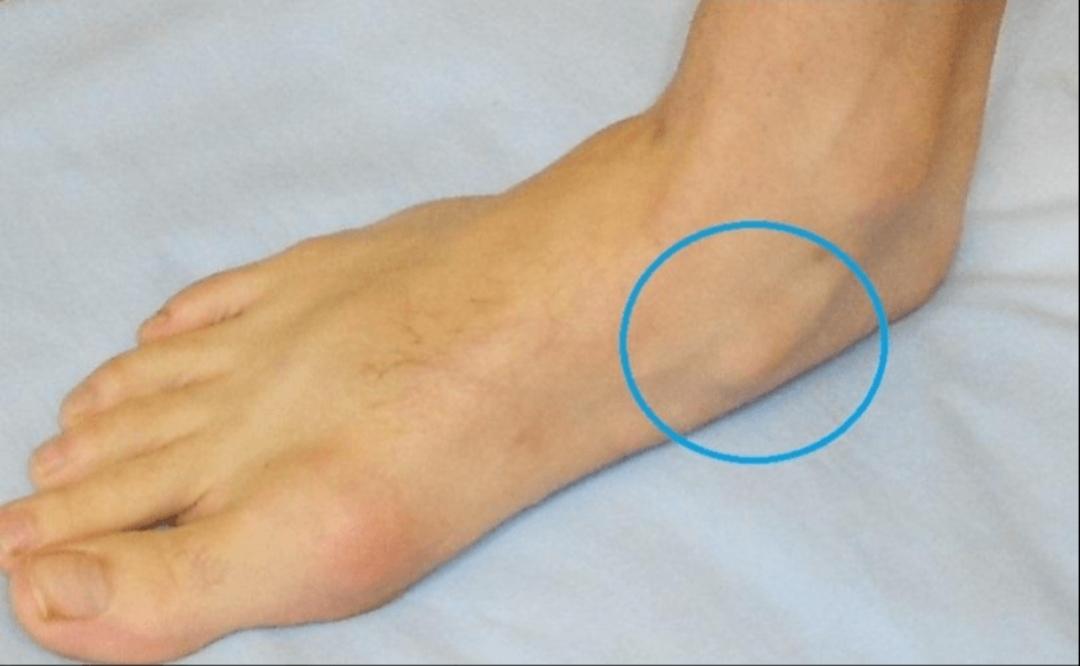

하키스케이트를 입문하면서 특히 아프던 발이 최근에 보니 복숭아 뼈만큼 튀어 나왔더라구요. 오른발이 심한 상태인데 왼발과 차이가 심하게 납니다. 전혀 아프지는 않는데 검색을 조금해보니 아프진 않아도 문제가 된다는걸 본거같아요.

부주상골(accessory navicular)은 발 안쪽 주상골(navicular bone) 옆에 추가로 존재하는 부골입니다. 전체 인구의 약 10에서 15퍼센트에서 관찰되며, 대부분은 무증상입니다. 특히 제2형(Type II) 부주상골은 후경골건(posterior tibial tendon)이 부착되는 부위와 연관되어 운동 시 통증을 유발할 수 있습니다.

정리하면, 현재 무증상이라면 경과 관찰이 원칙입니다. 다만 운동량이 많고 돌출이 뚜렷하다면 단순 방사선 촬영으로 형태를 확인해두는 것은 의미가 있습니다. 통증, 붓기, 운동 시 불편감이 생기면 그때 정형외과 진료를 권합니다.